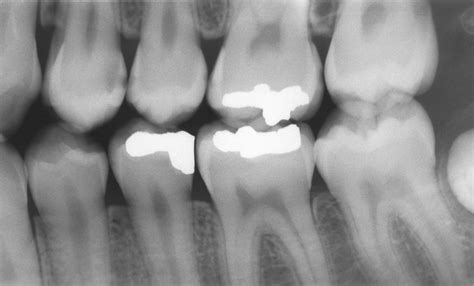

Periodontal Assessment & Saliva Testing - Thermography for Health New York